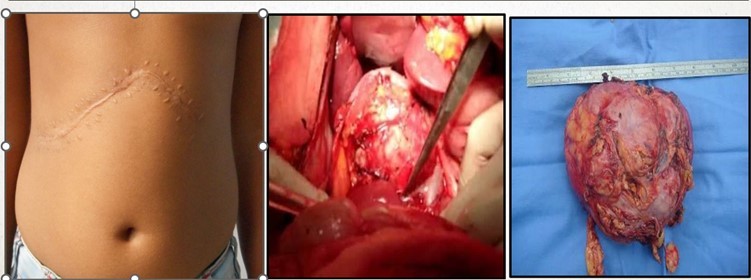

Figure 4: Right adrenalectomy and specimen photo

(Sensitive content- Click on the image to view)